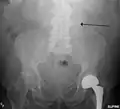

An abdominal aortic aneurysm is usually diagnosed by physical exam, abdominal ultrasound, or CT scan. Plain abdominal radiographs may show the outline of an aneurysm when its walls are calcified. However, the outline will be visible by X-ray in less than half of all aneurysms. Ultrasonography is used to screen for aneurysms and to determine their size if present. Additionally, free peritoneal fluid can be detected. It is noninvasive and sensitive, but the presence of bowel gas or obesity may limit its usefulness. CT scan has nearly 100% sensitivity for an aneurysm and is also useful in preoperative planning, detailing the anatomy and possibility for endovascular repair. In the case of suspected rupture, it can also reliably detect retroperitoneal fluid. Alternative less often used methods for visualization of an aneurysm include MRI and angiography.